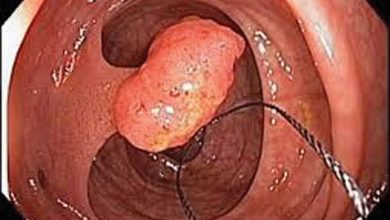

Colon Polyps

Digestive Health By Dr Saravana.K Colonic polyp is a small clump of cells that forms on the lining of the…